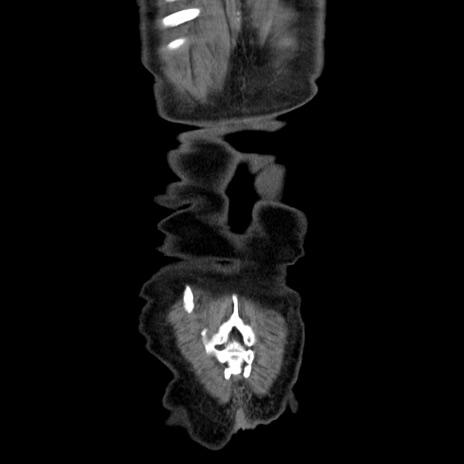

症例30(冠状断像)

横断像